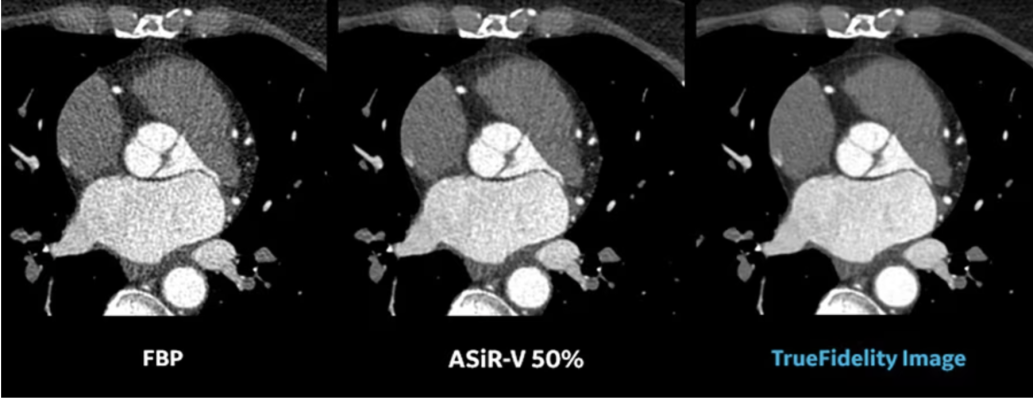

- TrueFidelity DL is available across the company’s Revolution Apex and Revolution Ascend platforms, leveraging a DNN to generate high-definition, low-noise CT images with exceptional sharpness, low-contrast image quality with preferred noise textureiii, at the same dose.iv GE HealthCare is also excited to expand TrueFidelity DL to lung and extremity at this year’s show. Exclusively available on Revolution Apex platform, these new features enable high resolution imaging to increase visual sharpness with reduced noise for confident reporting and accepted image texture.

iii As demonstrated in a clinical evaluation consisting of 40 cases and 6 physicians, where each case was reconstructed with both DLIR and ASiR-V and evaluated by 3 of the physicians. In 92% of the reads, DLIR’s noise texture was rated better than ASiR-V’s. This rating was based on each individual reader’s preference.

iv Image quality comparisons were evaluated by phantom tests of MTF, SSP, axial NPS, standard deviation of image noise, CT Number accuracy, CNR, and artifact analysis. Additionally, LCD was demonstrated in phantom testing using a model observer with the head and body MITA CT IQ Phantoms (CT191, CT189 The Phantom Laboratory). DLIR-H and ASiR-V reconstructions were performed using the same raw data.